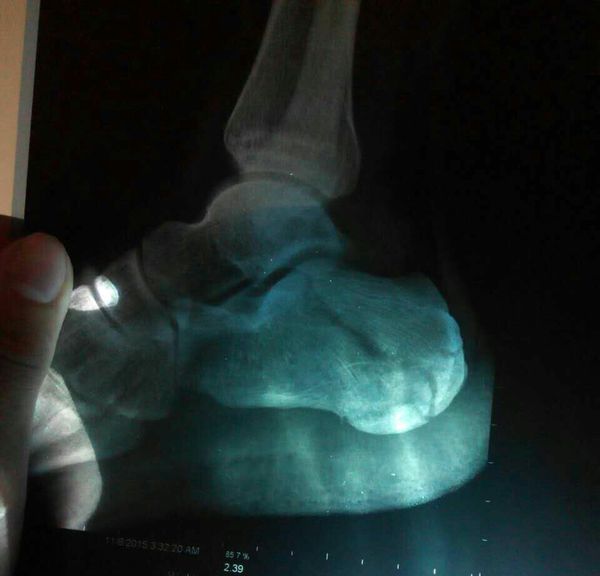

请问这个跟骨骨折严重吗?已经打了石膏

520x390 - 20KB - JPEG